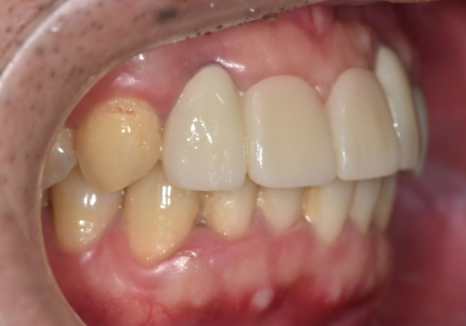

치료 결과

앞니 브릿지 부러짐,

이런 상태라면 절대 브릿지 다시 하지 마세요.

식립한 임플란트 기둥이

뼈와 완벽하게 하나로 결합하는

'골유착' 과정을 거치기 위해

임플란트 식립 후

약 5개월이라는 시간을 기다렸습니다.

그 후, 단단하게 고정된 것을 확인한 뒤

정밀 스캐너로 본을 떠서

최종 지르코니아 보철물을 제작해 드렸습니다.

특히, 이전 보철물을 사용하실 때

앞니가 유독 튀어나와 보였다고 하셔서,

이 부분을 충분히 고려하여

정교하게 보철을 제작하도록 신경썼는데요~

덕분에 치열이 한층 가지런해진 것은 물론이고

이전보다 입매가 안쪽으로 들어가 보여

전체적인 인상 자체가

훨씬 부드럽게 개선되었습니다.

기능적인 회복은 물론 심미적인 부분까지

자연스럽게 마무리되어,

환자분도 저도 많이 만족했던 케이스였네요^^